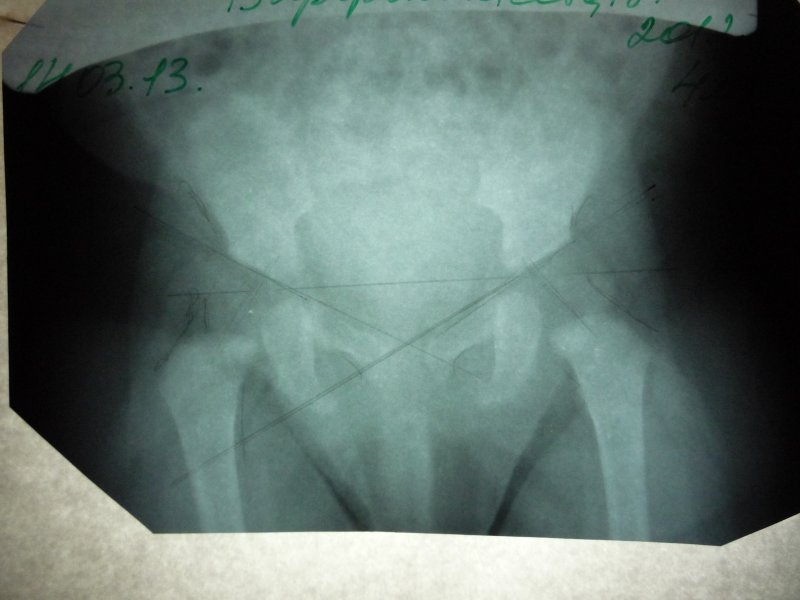

Здравствуйте! посмотрите пожалуйста .Извините за качество ,сам снимок не очень(это один и тот же снимок )

Снимок очень плохого качества, практически не читается. Я не рискну давать Вам рекомендации по такому снимку. Сколько сейчас Вашему малышу?